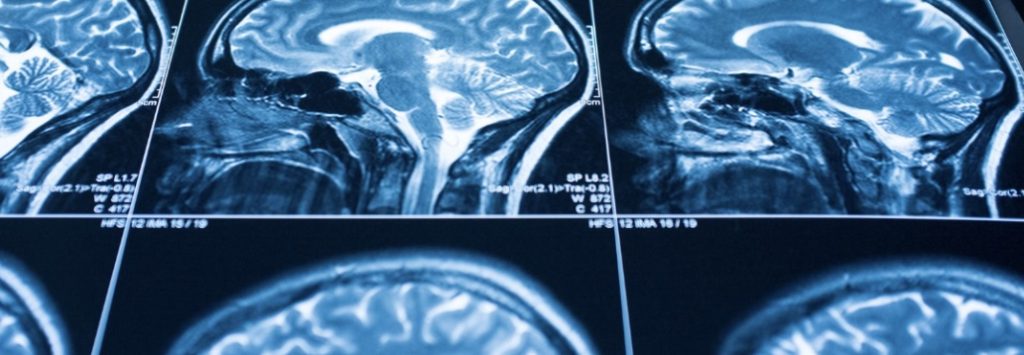

DEAD END FOR FAILED EXPERT OPIOID CRISIS FIXES: IMPAIRING BRAIN INJURY BY UNRELENTING OVERDOSE WITH SERIAL EMERGENCY NARCAN REVERSALS

DEAD END FOR FAILED EXPERT OPIOID CRISIS FIXES: IMPAIRING BRAIN INJURY BY UNRELENTING OVERDOSE WITH SERIAL EMERGENCY NARCAN REVERSALS In the absence of prevention efforts or provision of evidence-based treatments, an expert-driven cycle of high-risk use, overdose, emergency Narcan revivals, and induced brain injury can only spiral downward by Clark Miller Published September 26, 2025 […]